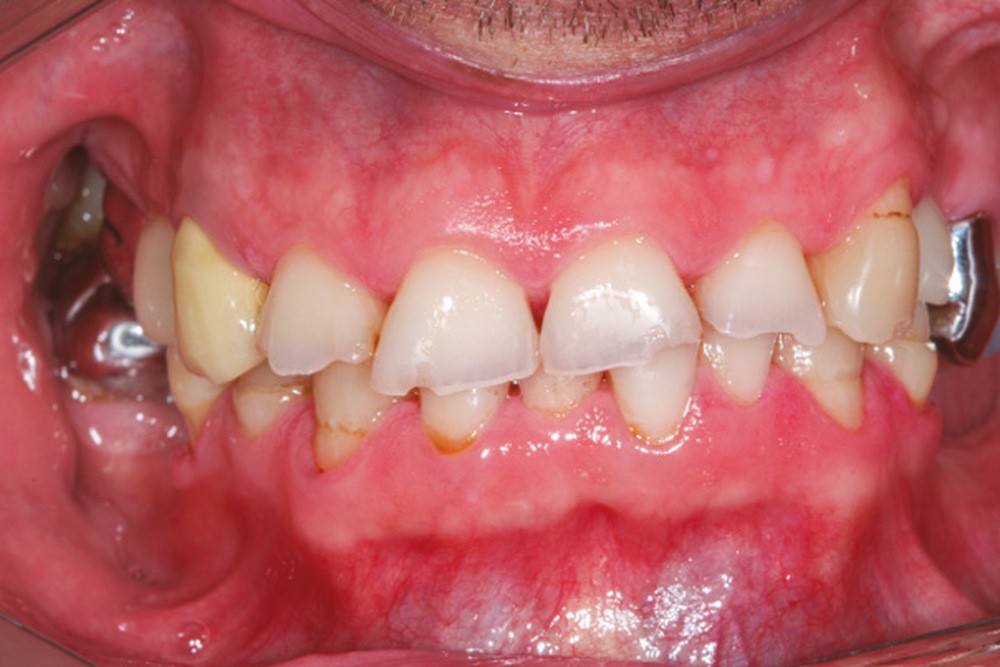

La perte d’une ou plusieurs dents entraîne la perte des points de contact, responsables de la stabilité et de la continuité de l’arcade. Par conséquent, une avulsion a pour première conséquence la migration ou la version d’une ou plusieurs dents distales (fig. 1 et 2). Cela est vrai en antérieur comme en postérieur.

L’âge de survenue de l’extraction semble avoir une importance sur l’apparition des migrations et des versions : si l’édentement intervient après 26 ans, les conséquences sont moins fréquentes [9].

Cette version, quand elle se produit, modifie les espaces interdentaires et complique l’hygiène proximale des patients. Des caries peuvent alors se développer en interproximal sans que cela soit forcément visible à l’examen visuel (fig. 3 et 4). Les radios de type bite-wing (rétro-coronaires) prennent alors tout leur sens (fig. 5 et 6).

La version des dents distales peut aussi avoir des conséquences parodontales désastreuses : sur un parodonte réduit, une hypermobilité peut se développer, une poche parodontale peut aussi apparaître. Chez un patient parodontal, un « effet domino » est possible, des extractions non compensées diminueront donc le pronostic des dents restantes (fig. 7 à 9).

Le principe de protection mutuelle implique que les dents postérieures protègent les antérieures lors de la mastication. Des extractions non compensées de molaires, par exemple, entraîneront une hypersollicitation des antérieures et une usure importante du fait du principe de calage ainsi qu’un risque de perte de dimension verticale (fig. 10 à 13).